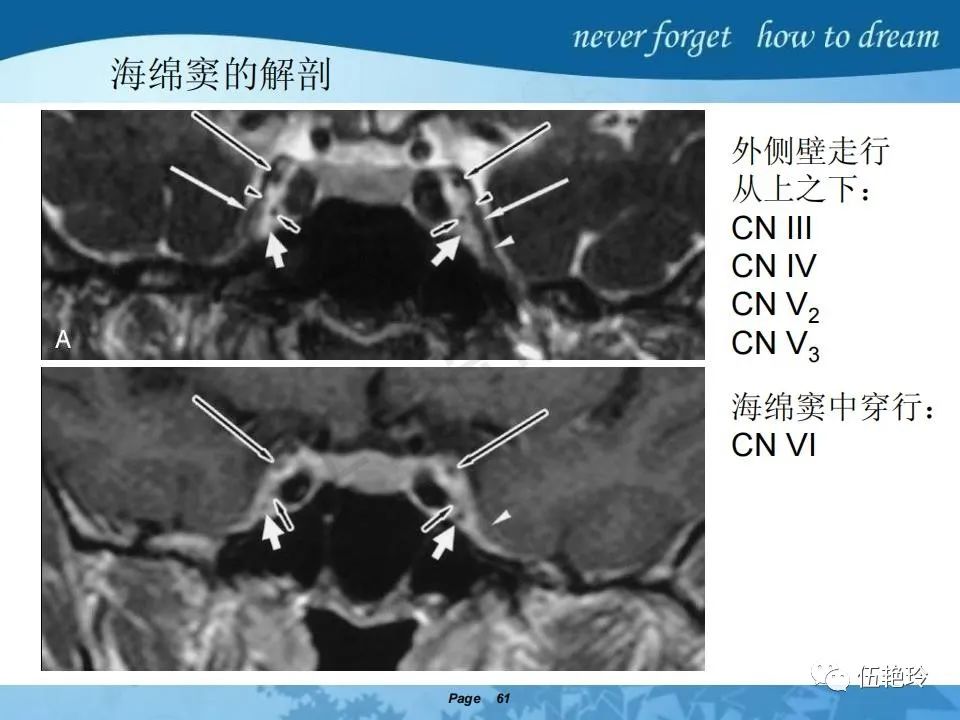

海绵窦区的解剖结构与鼻咽癌侵犯

2.31 向上颅内:①鼻咽顶壁→破裂孔(岩尖、斜坡)→蝶窦、海绵窦;②鼻咽顶壁→蝶骨基底部→蝶窦、海绵窦;③鼻咽侧壁→茎突前间隙→蝶骨大翼(卵圆孔)→海绵窦;④鼻咽侧壁→茎突前间隙→翼腭窝→ 颞下窝;⑤鼻咽前壁→鼻腔→翼突、翼腭窝→眶下裂→眶尖→海绵窦;⑥鼻咽前壁→鼻腔→上颌窦、筛窦;